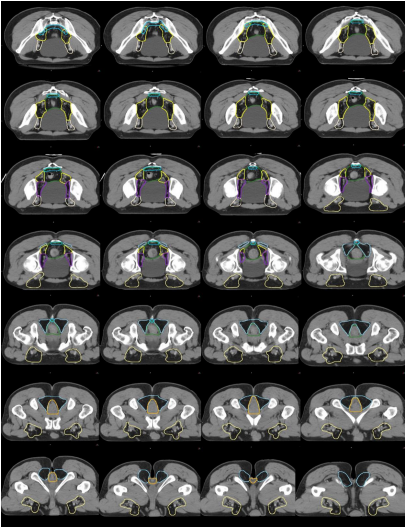

i) 高危復發區合集圖(CT 層厚 0.5 cm,俯臥位)(圖 14)。下表 示出高危復發區顏色。

表 直腸癌高危復發區顏色

圖 14 直腸癌高危復發區合集圖